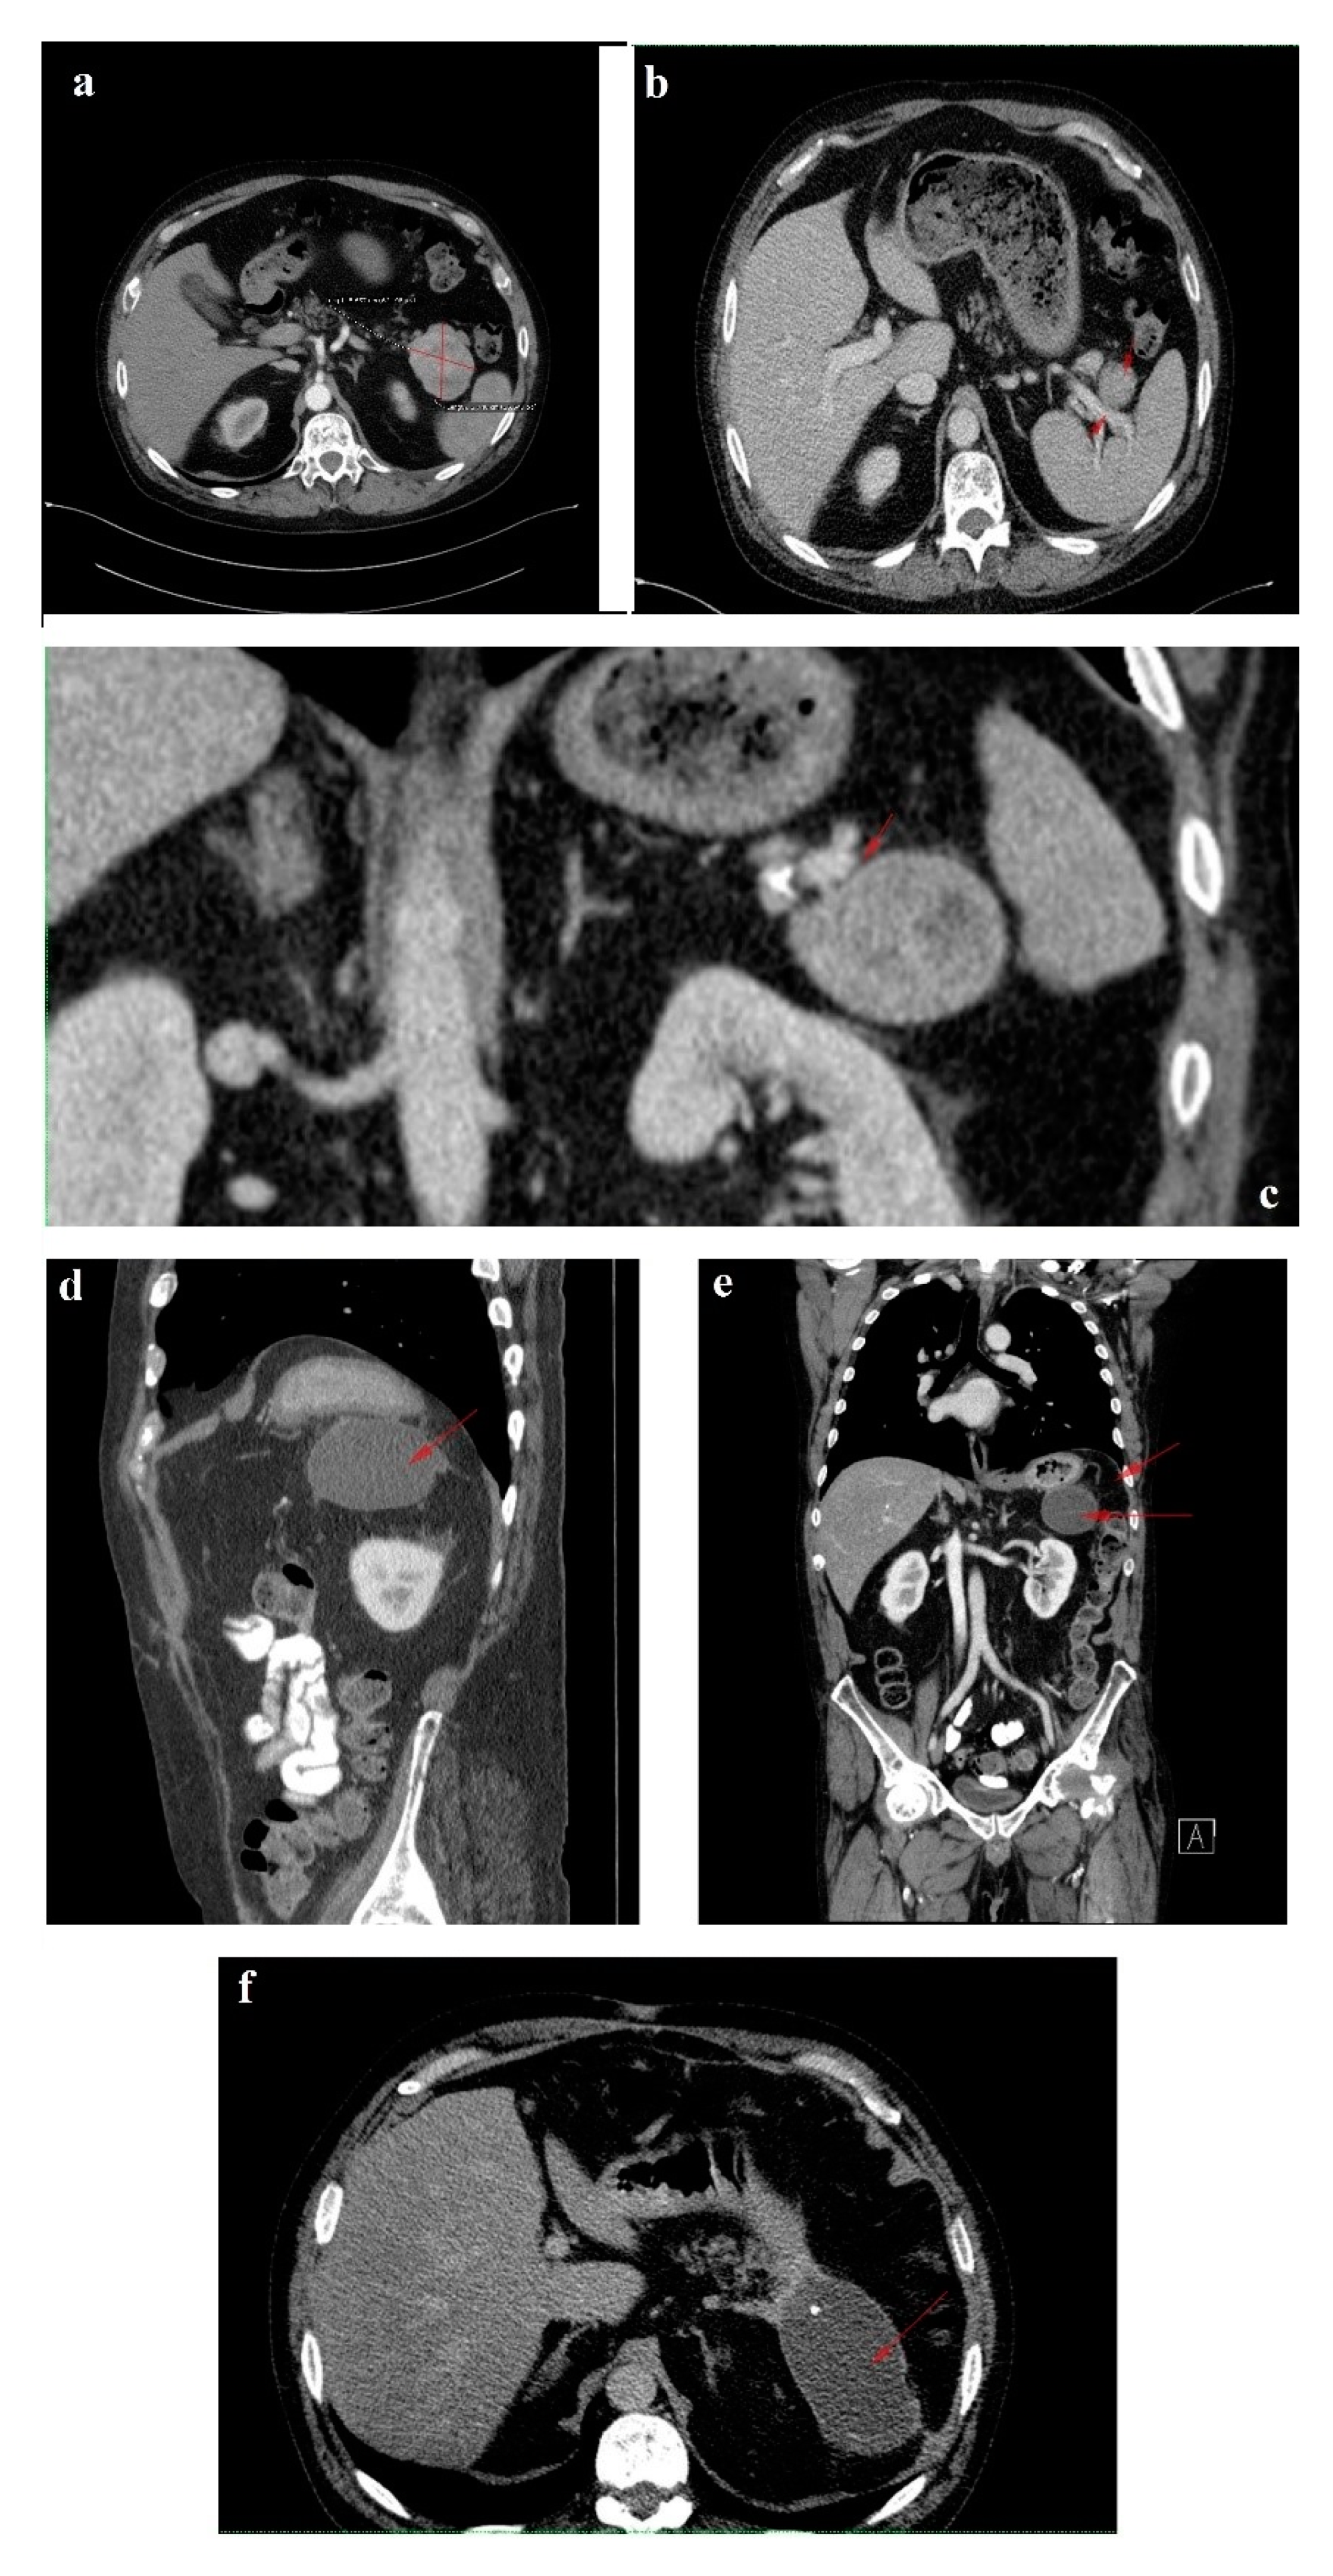

In February 2018, upon presentation to our department of endocrinology, the clinical examination revealed a middle-aged male patient unable to walk unassisted or without a frame, with severe bilateral hip arthralgia, slightly elevated blood pressure (150/90 mmHg) and tachycardia (heart rate = 110 bpm). The laboratory tests revealed normocytic normochromic anemia (Hb = 11 mg/dL), hypoproteinemia (5 g/dL), elevated inflammatory markers (ESR = 91 mm/h, fibrinogen = 668 mg/dL, high sensitivity CRP = 73.7 mg/L), high glycated hemoglobin (HbA1c = 7.6%), normal chromogranin A (CgA) and 5-hydroxyindoleacetic acid (5-HIAA), and elevated plasma glucagon levels (2130 ng/L, N < 209) that confirmed the positive diagnosis of glucagonoma syndrome. Biochemical screening for MEN 1 syndrome was negative (serum calcium = 8.3 mg/dL, PTH = 32.62 pg/mL, 25 hydroxy vitamin D = 27.27 ng/mL, prolactin = 12 ng/mL, IGF1 = 114 ng/mL). A multiphasic contrast-enhanced CT diagnosed a 35/44 mm tumor with heterogenous texture located in the pancreatic tail, multiple peritumoral nodules suggestive of locoregional metastases, two incompletely consolidated fractures at the sixth and seventh ribs, and a reduction in bone density and the height of the thoracolumbar vertebras (Figure 3a–c).

For disease staging, we performed whole body 18F fluorodeoxyglucose-positron emission tomography (FDG-PET)/CT, which revealed a 34/38 mm hypermetabolic (standardized uptake value (SUV) = 6.67) tumor in the pancreatic tail and satellite solid tumors nearby the primary tumor with no uptake of F-18 FDG. There was no imaging proof of systemic metastases. Using whole body 99mTc-EDDA/HYNIC-Tyr3-Octreotide scintigraphy (SRS) with single photon emission tomography (SPECT-CT) acquisition we noticed a 41/33 mm well-circumscribed pancreatic tumor with high radiotracer uptake. The pancreatic tumor was the only situs for the radiotracer uptake (Figure 5).

The six month follow-up in September 2018 was uneventful, with the glucagonoma syndrome well controlled on SSA therapy, normal plasma CgA, decreasing glucagon levels (863 ng/L) and stable disease on CT (Figure 3d). It is important to mention that the patient received treatment with vitamin K antagonists for the deep vein left leg thrombosis and displayed high fluctuations in INR values. Despite our plan for the tumor surgical resection, the preoperative biological check-up revealed an INR value of 14, which prompted intravenous phytonadione administration. The INR reached the therapeutic range; however, the patient developed sagittal sinus thrombosis that was eventually favorably managed by the department of neurology.

In October 2019, a follow-up abdominal multiphasic contrast-enhanced CT showed small-scale tumor progression and the patient was scheduled for surgery again (Figure 3e). The echocardiography performed during the preoperative cardiologic evaluation revealed hypokinesia of the ventricular septum; akinesia of the basal segment of the inferior wall; akinesia of the medium segment of the inferolateral, lateral and anterior walls; and severe left ventricular dysfunction with an ejection fraction of 28%. Coronary angiography uncovered trivascular atherosclerotic disease, and a percutaneous angioplasty with stent implantation was performed. The surgical intervention was postponed again.

Regrettably, in the spring of 2020 the COVID-19 pandemic reached our country and follow-up was possible only in July 2020, when, despite clinical control, the tumor (52/45 mm) and the peritumoral nodules had progressed; however, no hepatic or bone metastases were detected during morphological imaging (Figure 3f). As expected, we attempted surgery once more. This time, the patient was infected with SARS-CoV-2 and, by an unexpected fortunate chance, he had a completely asymptomatic infection.

Figure 3. 1 February 2018 CT scan: (a) axial image without contrast showing a round solid mass with microcalcification in the tail of the pancreas; (b) arterial phase coronal reconstruction showing a hypervascular mass with satellite nodules situated in the pancreatic tail; and (c) axial image, arterial phase showing a 35/44 mm tumor in the pancreatic tail. September 2018 follow-up CT: (d) axial image, arterial phase showing stable disease. October 2019 follow-up CT: (e) axial image, arterial phase showing inhomogeneous contrast enhancement and small-scale tumor progression. July 2020 follow-up CT: (f) axial image, arterial phase showing evident tumor mass progression.